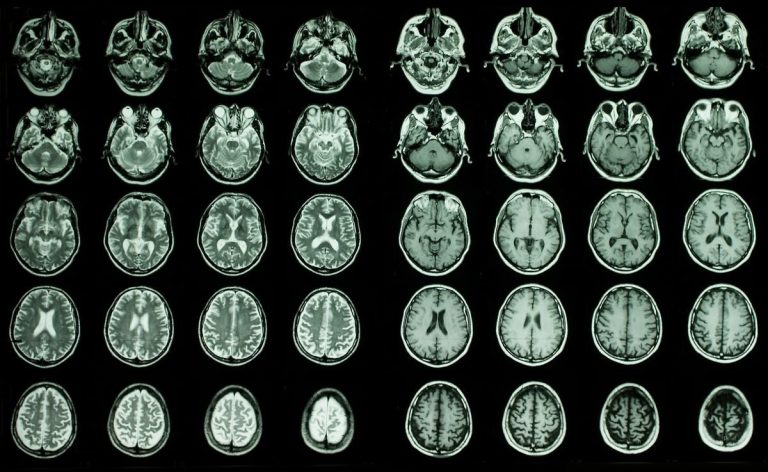

Исследователи обнаружили 13 белков в крови, которые, по-видимому, связаны со старением мозга

Исследователи изучили данные сканирования мозга и результаты анализов крови, чтобы найти корреляцию между определенными белками и старением мозга. Китайские неврологи